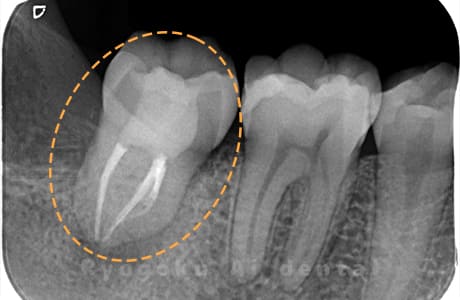

Case01

-

- 原因

- 慢性根尖性歯周炎

- 治療期間

- 3ヶ月

- 治療内容

- 自家歯牙移植手術+マイクロエンド+ダイレクトボンディング

- 治療費用

- ¥220,000

他院で根尖病変が大きく、抜歯と判断され、インプラント手術を提案された患者様です。親知らずが残存していたため、自家歯牙移植手術を行いました。

<リスク・副作用>

治療後、痛みや違和感、出血、腫れなどが出る事があります。喫煙者、糖尿病などの方の場合、歯が生着しない場合があります。